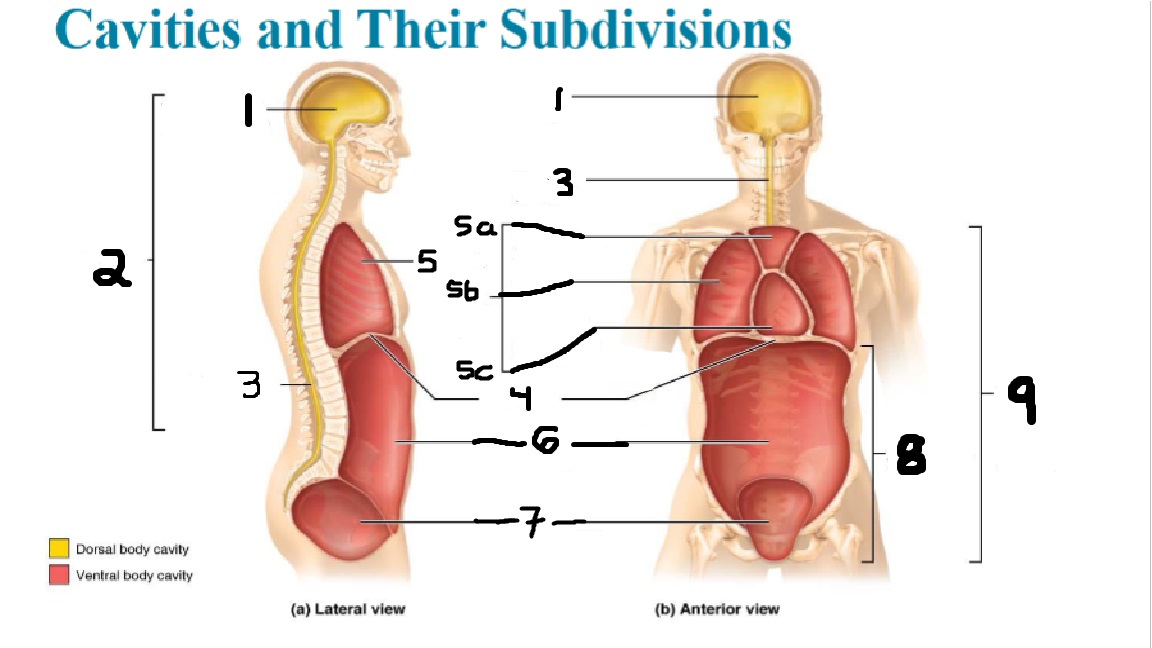

What cavities are part of the dorsal cavity?

The cranial and the Spinal (vertebral) cavities

What kind of cavity is labeled 2?

The dorsal body cavity (containing the cranial and spinal cavities)

What is the purpose of the dorsal cavity?

protects the nervous system

What is the main organ encased by the cranial cavity?

the brain

What cavity is labeled #1?

The cranial cavity

What is the main organ encased by the vertebral cavity?

the spinal cord

What is another word for the vertebral cavity?

the spinal cavity, or the spinal canal

What body cavity is labeled 3?

the vertebral cavity.

What cavities are included in the ventral cavity?

the thoracic, abdominal, and pelvic cavities.

What body cavity is labeled #6?

the abdominal cavity.

What are the main organs of the abdominal cavity?

the digestive organs such as the stomach, intestines, spleen and liver

What cavities are included in the Abdominopelvic cavity?

the abdominal cavity and the pelvic cavity

What body cavity is labeled #8?

The Abdominopelvic cavity

What does the diaphragm separate?

the thoracic and the abdominal cavities

What is labeled #4?

the diaphragm

What organs does the pelvic body cavity contain?

urinary/reproductive organs and rectum

What is labeled #7?

the pelvic cavity

What does the thoracic cavity encase?

the heart and the lungs

What is labeled #5?

the thoracic cavity

What part of the thoracic body cavity is labeled 5a?

superior mediastinum

What part of the thoracic body cavity is labeled 5b?

pleural cavity

What part of the thoracic body cavity is labeled 5c?

pericardial cavity within the mediastinum

What body cavity encloses the heart?

the pericardial cavity.